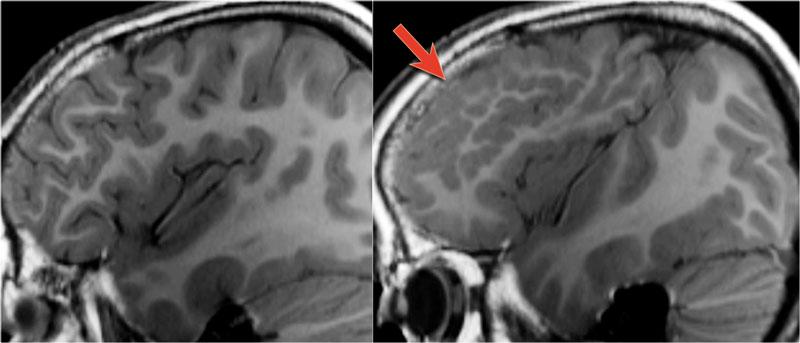

Sẹo vỏ não và sẹo thần kinh đệm – Ulegyria

Bệnh nhân 54 tuổi có tiền sử ngạt chu sinh và động kinh cục bộ kháng trị kéo dài. Sẹo thùy đỉnh trái tại vùng phân thủy cạnh đường giữa gây teo vỏ não.

Sẹo vỏ não và sẹo thần kinh đệm thường là hậu quả của viêm màng não hoặc chấn thương lúc sinh.

Ulegyria là một dạng sẹo đặc biệt.

Được định nghĩa là tình trạng sẹo hóa vỏ não do thiếu máu cục bộ chu sinh.

Ulegyria thường gặp ở trẻ sinh đủ tháng.

Ở những trẻ này, tưới máu tại đỉnh các hồi não nhiều hơn so với vỏ não ở đáy các rãnh não.

Hình ảnh điển hình là vỏ não bị teo, trong đó phần sâu của các hồi não bị teo nhiều hơn phần nông, tạo nên các hồi não có cuống dài với hình ảnh giống cây nấm.

Ulegyria cần được phân biệt với microgyria (hồi não nhỏ).

MRI sẽ cho thấy hình ảnh mất mô não và tăng sinh thần kinh đệm (gliosis) bên dưới vỏ não bị teo.

Vỏ não bị teo được đánh giá rõ nhất trên chuỗi xung T1W 3D do độ phân giải cao và khả năng phân định vỏ não vượt trội, trong khi chuỗi xung FLAIR sẽ cho thấy tăng tín hiệu liên quan đến tình trạng gliosis.

Do đó, cần luôn sử dụng chuỗi xung FLAIR để tìm kiếm các vùng tăng tín hiệu ở bệnh nhân động kinh, sau đó đối chiếu các phát hiện này với vỏ não tại vùng tổn thương trên chuỗi xung T1W độ phân giải cao.